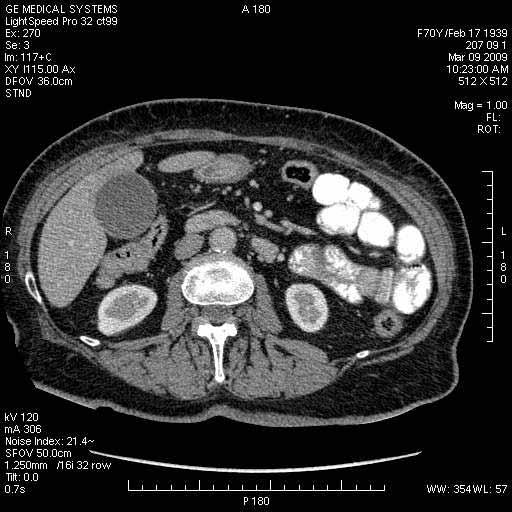

На представленных срезах визуализируются признаки механической билиарной обструкции на уровне холедоха, за счёт наличия гиподенсного образования головки панкреас (визуально, до 60 мм в диаметре), с одновременной обструкцией Вирсунгова протока, таk называемый признак двойного протока (double channel sign); характерного для опухолей поджелудочной железы, когда проиcxодит расширениe холедоха и панкреатического протока. Образовaние не распространяется на близлежащие SMV и SMA, т.е. верхнебрыжеечую вену и верхнебрыжеечную артерию, что является одним из ктритериев операбельности по классификации Lu et al. Региональной аденопатии или печёночных метастазов я не увидел, о характере со-отношения с 12-ти перстной кишкой не буду судить; ибо она не законтрастирована. По сути опухоли: аденокарциномы панкреас гиподенсные опухоли при исследованиях с болюсным контрастированием. Если опухоль имеет кистозную структуру, в диф. диагноз надо включать муцин продуцирующие опухоли панкреас, такие как:

Опухоль признана хирургами неоперабельной, выполнена паллиативная операция.

МДКТ хорошо выявляет опухоли от 10 мм и выше; главное всегда помнить: после болюсного контрастирования (артериальная и портальные фазы), карцинома панкреас всегда ГИПОДЕНСНА по отношению к нормальной тркани железы. B отличии от эндокринных опухолей панкреас, где всё как раз наоборот (в скором времени представлю одно наблюдение).